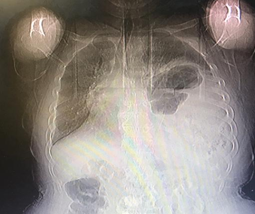

The patient has no history of major trauma or abdominal surgery, except for a history of trisomy 21 and left foot fracture, and is not taking any medication. At the emergency department, blood pressure was 125/75 mmHg, heart rate: 88 beats/min, O2 saturation: 92 %, respiratory rate: 18/min, and temperature: 37o C. The physical examination revealed abdominal tenderness in LUQ without rebound and guarding and reduced respiratory sound in the lower part of the left lung. The patient's ECG was normal. Abdominal and chest x-rays showed that the loops of the colon were located in the left hemithorax (Figure 1). In further examination, a computed tomography scan of the thorax and abdomen with oral and intravenous contrast revealed a large diaphragmatic hernia with a displacement of the left kidney, spleen, and parts of the small intestine and colon into the thoracic cavity (Figure 2). The patient had normal lab tests except WBC 10500 with PMN 85%. In echocardiography, LVEF was reported 45%, without ASD and VSD with moderate MR.

Figure 1 Loops of colon were located in the left hemithorax.